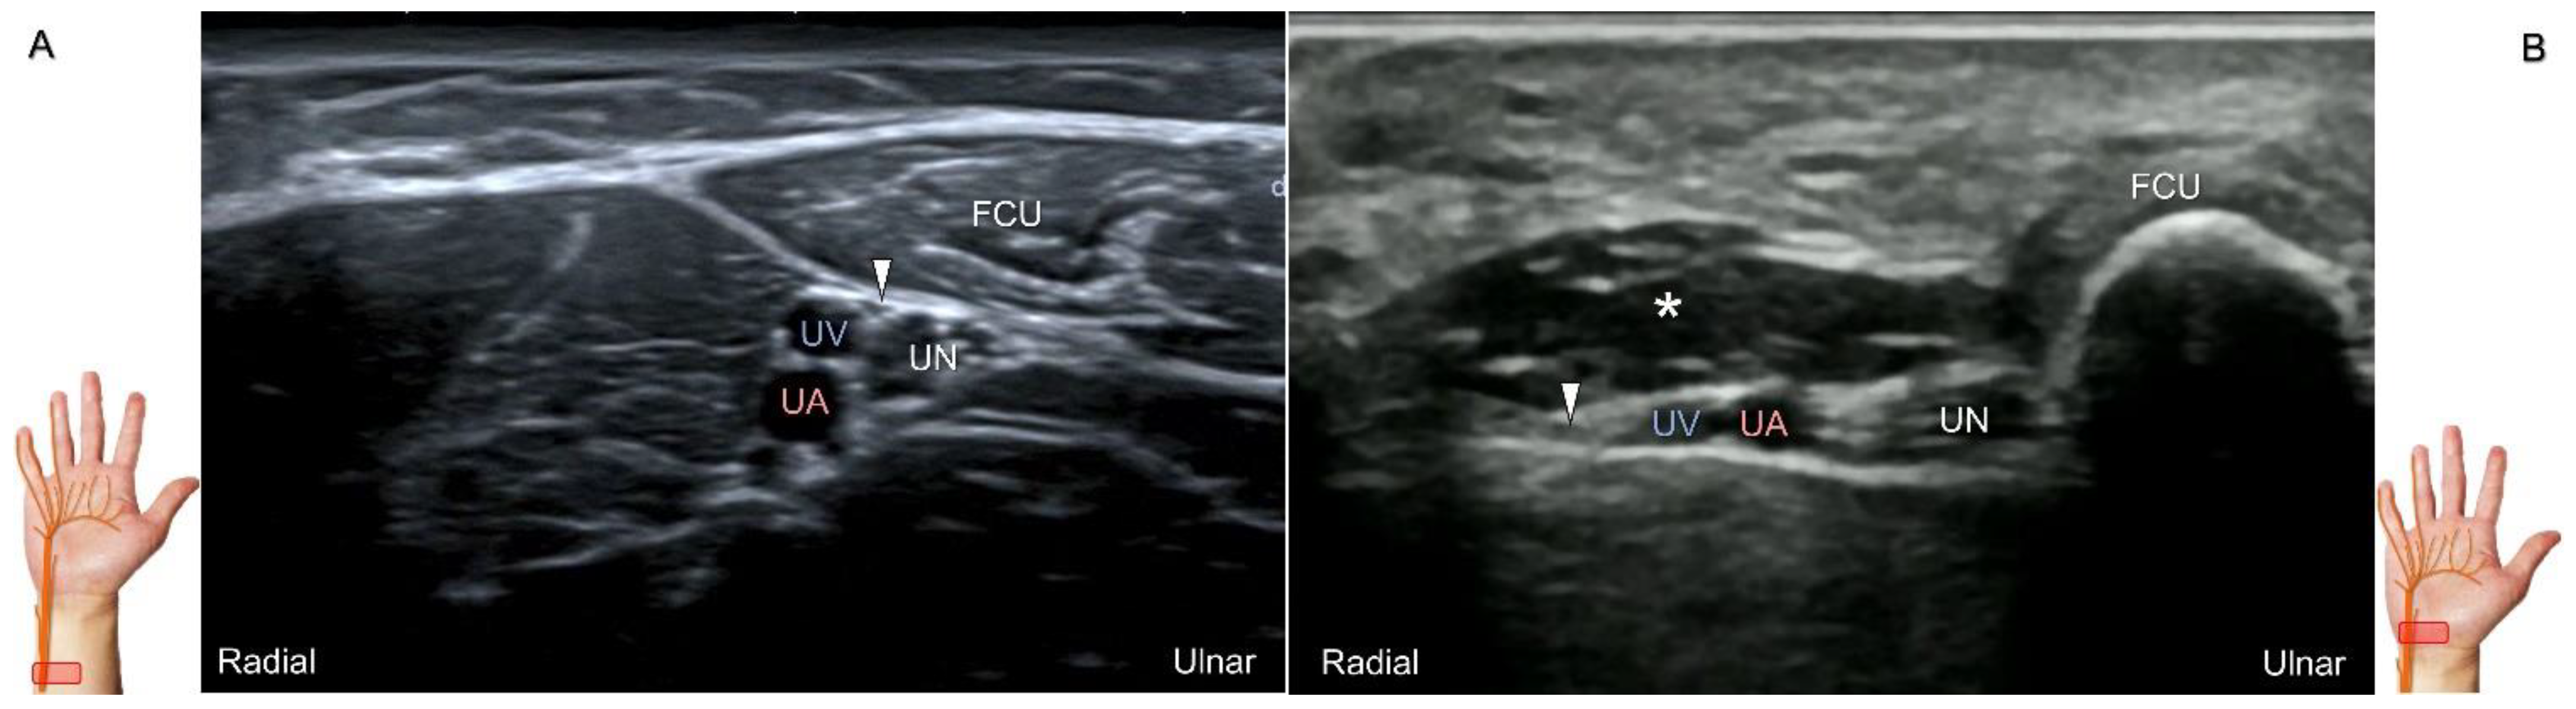

During scanning, the forearm is supinated with the transducer placed along the axial plane of the distal forearm. Moving the transducer more distally, the palmar ulnar cutaneous nerve can be seen as a single hypoechoic fascicle departing from the radial side of the main trunk near the bifurcating point for the dorsal ulnar cutaneous nerve (Figure 18A). It is crucial to apply light touch without compressing the adjacent vein, which can be used to highlight the nerve’s border.

Clinical Implication

The palmar ulnar cutaneous nerve has been associated with certain peripheral vascular disorders that can lead to arterial constriction and erythema over the hypothenar eminence [42]. The nerve may be persistently entrapped due to the presence of an accessory abductor digiti minimi muscle (Figure 18B) [42].

Figure 18. Sonographic imaging (short-axis view) of the palmar ulnar cutaneous nerve (A) and its entrapment in the presence of an accessory abductor digiti minimi muscle (B). Arrowhead: palmar ulnar cutaneous nerve; asterisk: accessory abductor digiti minimi muscle. UN: ulnar nerve; UA: ulnar artery; UV: ulnar vein; FCU: flexor carpi ulnaris tendon.

Diagnostics 13 01928 g018